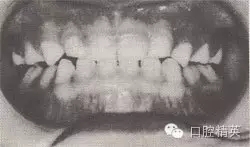

治療時(shí)間:1.5個(gè)月,乳前牙反頜解除,乳切牙達(dá)到正常覆頜、覆蓋。下頜回到正常位置。

圖8-37 安氏Ⅲ類錯(cuò)頜,乳前牙反頜矯治前后面頜像

矯治前咬合圖

矯治后咬合圖